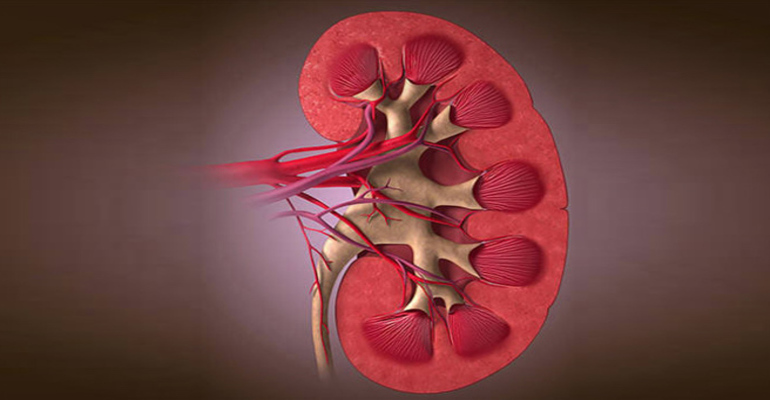

Ελλάδα Κέντρο Αιμοκάθαρσης: Ο απίστευτος παράγοντας που συμβάλλει σε έμφραγμα, εγκεφαλικό και νεφροπάθεια

Ερευνητές από το Πανεπιστήμιο της Αριζόνα διαπίστωσαν ότι ένας «ύπουλος» παράγοντας μπορεί να υπονομεύσει σημαντικά την υγεία μας και να μας βάλει μελλοντικά σε κίνδυνο, καθώς αυξάνει τις πιθανότητες να πάθουμε έμφραγμα ή εγκεφαλικό και να εμφανίσουμε πρόβλημα στα νεφρά ή τα μάτια.